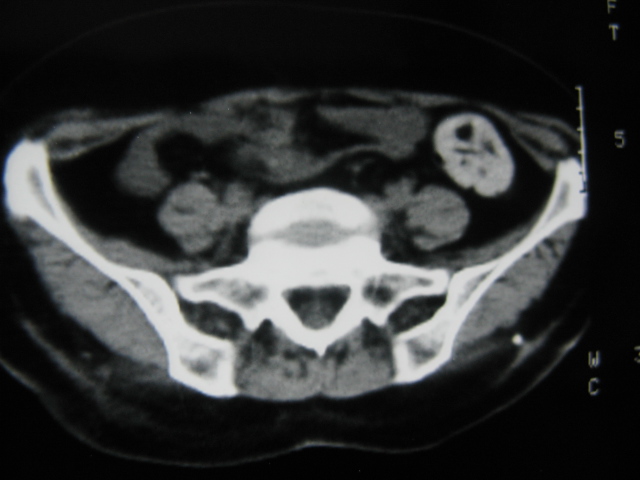

患者,女,64岁,2002年诊断为宫颈癌,当时只做过放,化疗。现在诊断:(1)宫颈癌。(2)直肠癌。请同道们讨论,探讨。另外肠壁为啥密度这么高,ct值约112hu。患者没有做过增强和造影。

高密度的不是肠管影,是肠管内的粪便影

患者直肠病变,排便不畅,粪便硬结造成,更高密度如钡灌肠者都可出现

硬结粪便能有如此高密度影?

我也碰到过几例,最离奇的一例是全结肠呈造影样高密度,患者直肠癌(首次发现),以往没有吃药,只有约半年时间长的胃纳差,排便不畅(据患者说每次大便只能拉出少许黄水)

不一定有意义,可清洁灌肠后复查